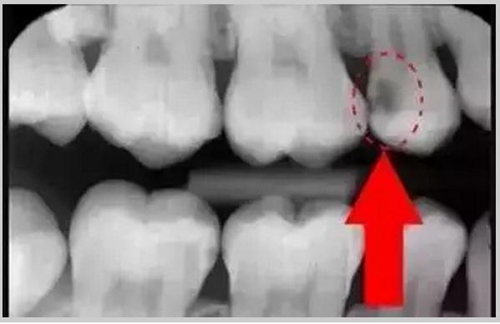

從上圖中可以知道除了外層的一點(diǎn)牙釉質(zhì),牙齒里面出了問題,肉眼是無法觀察到的。牙醫(yī)不長透視眼當(dāng)然不能透過現(xiàn)象看到牙齒本質(zhì)嘍。因此,為了對(duì)牙齒進(jìn)行全面的了解,拍個(gè)牙片還是很有必要的。